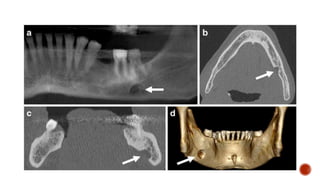

 Benign but locally aggressive odontogenic tumor

 Typical location-posterior mandible (posterior body and ramus).

 Painless swelling/incidental

 Septations within the lesion -“honeycomb” or “soap bubble” appearance.

 The lesion usually shows marked buccolingual expansion with cortical

thinning/breach . There may be accompanying teeth displacement and resorption.

 Enhancement of solid component on CT and MR.

 Cystic component with low T1W and high T2W signal.

 Diffusion restriction of solid component.